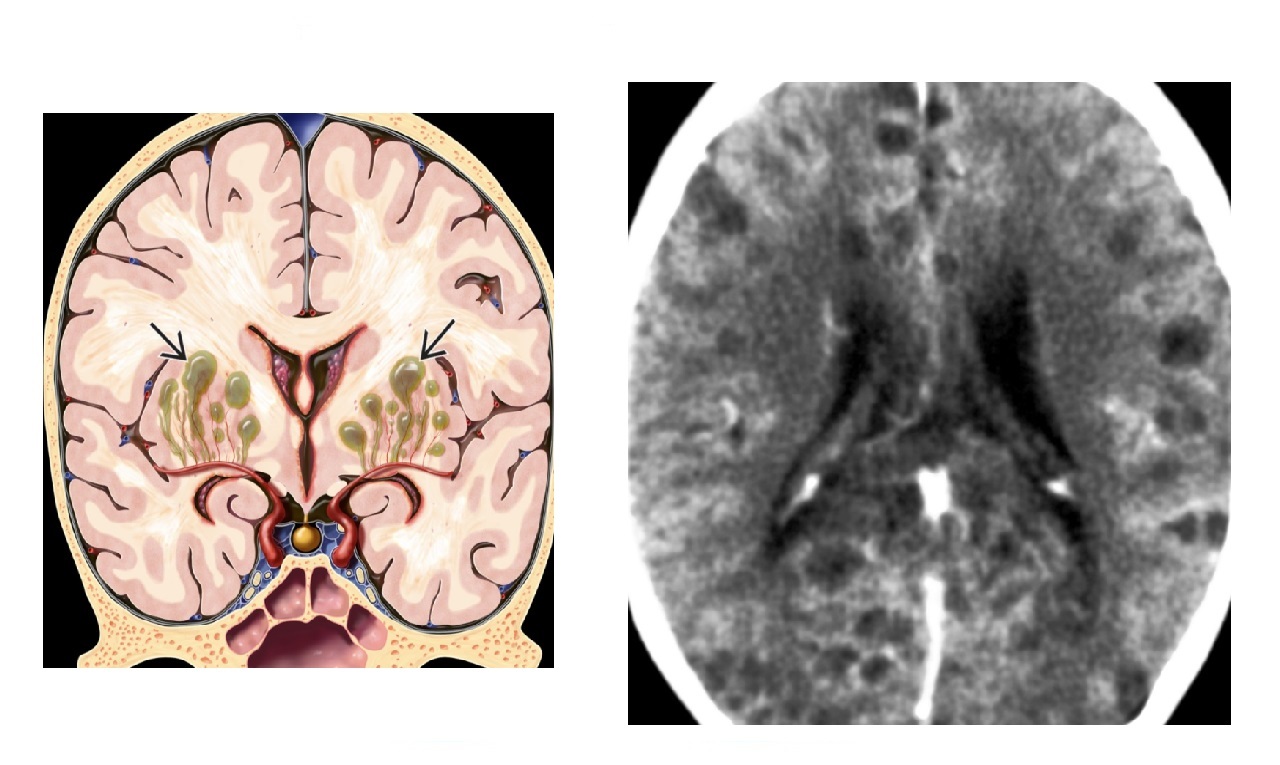

Key differences of lymphoma vs toxoplasmosis?

Lymphoma -

Solitary lesion

Subependymal spread/corpus callosum

Restricts DWI

Hyperdense on CT

HOT Thallium SPECT

Toxoplasmosis -

Multiple lesions.

Significant oedema - target sign

Basal ganglia

No restriction DWI

COLD Thallium SPECT